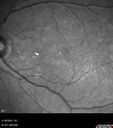

65 year old female Funny looking retinas referred by retina specialist Medical Hx: Hypertension, Systemic. Anxiety. Surgical Hx: Noncontributory. Systemic Meds: Amlodipine 5mg 1 tablet bid by mouth. Alprazolam, 0.5 mg oral tablet 1 tablet prn. buspirone hydrochloride 15 MG (as buspirone 13.7 MG) Oral Tablet 1 tablet bid. HCTZ 12.5 MG / Olmesartan medoxomil 20 MG Oral Tablet [Benicar HCT] 1 tablet qhs. VA 20/50 OU IOP 20 OU

Choroidal Melanocystosis85 views65 year old female with normal vision.00000